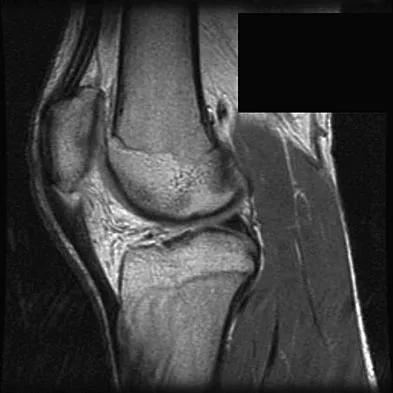

A 45-year-old male karate instructor sustained the injury shown in Figures 40a through 40c while practicing karate. The decision to proceed with surgery depends on which of the following factors?

Explanation

The most important criteria in determining the need for surgery following a nondisplaced or minimally displaced tibial plateau fracture is knee stability to varus/valgus stress. Soft-tissue injury noted on MRI may be addressed at a later time following fracture healing. This fracture pattern is amenable to nonsurgical management. Decisions regarding surgical intervention may be made up to 2 weeks after injury.